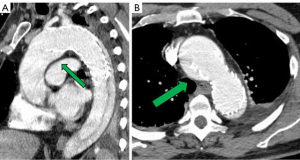

A 73-year-old asymptomatic primary care physician was referred to our Aorta Center with aortic arch and root aneurysms, and a chronic distal aortic dissection. The acute type B aortic dissection occurred two years earlier and was complicated by mesenteric ischemia requiring an emergency thoracic endovascular aortic repair (TEVAR) using a 45 mm × 150 mm stent graft device (CTAG, WL Gore and Associates, Flagstaff, AZ, USA) performed at an outside institution (Figure 1). He tolerated the procedure well with resolution of the ischemia and expansion of the true lumen. The postoperative course was uneventful, but he had persistent degeneration and growth of his aortic arch proximal to the stent-graft and through the descending aorta.